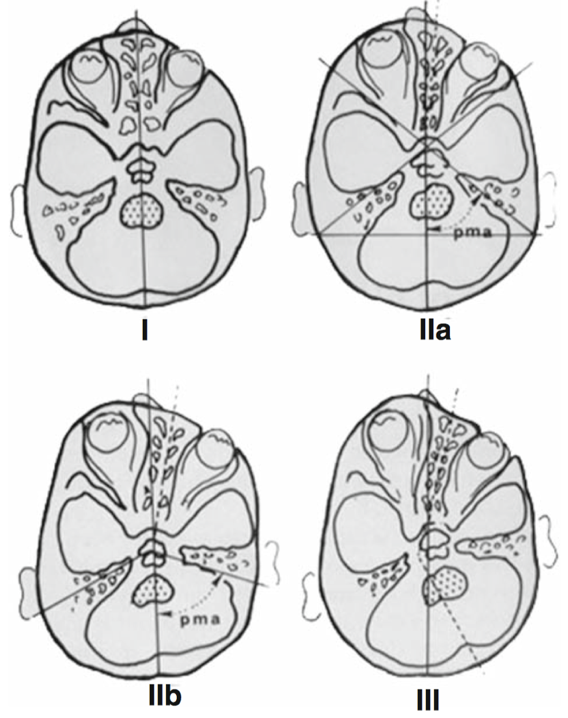

颅内动静脉畸形的诊断和评估,显微外科切除仍然是仔细选择的动静脉畸形的优选治疗方法,因为它可以立即明确地排除AVM。为此,已有许多AVM分类体系被...

脑动静脉畸形手术的现代分类及预后评估 (Modern classification and outcome predictors of surgery in patients with brain arteriovenous malformations) 英文摘要: Brain arterioveno...

功能区亚型是否影响 动静脉畸形手术 的预后? (Does eloquence subtype influence outcome following arteriovenous malformation surgery?) 英文简介: OBJECTIVE Although numerous art...